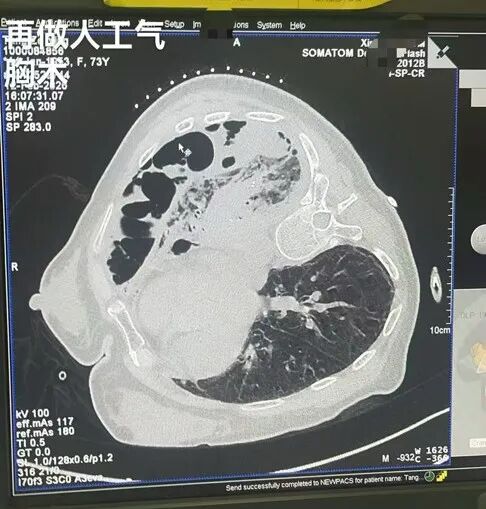

既然院前常规检查及胸膜活检没结果,就需要更深入的检查。但下一步能不能做胸腔镜检查?医生决定先做一个“人工气胸”术。团队在切线位胸膜活检术完成后,当即调整同轴活检针方向,同轴活检针进入胸膜腔后,抽出少量暗红色胸腔积液,送检病原学检查及脱落细胞学检查,并缓慢分次向患者胸腔内注入了500毫升过滤空气,这不仅可以促进肺组织缓慢压缩,还能通过气体分布情况观察胸膜腔的状态。结果:CT扫描下发现,注入的过滤空气在胸腔内分布极不均匀,存在严重的胸膜腔粘连,最大的空气腔室甚至不足3厘米。而传统内科胸腔镜检查要求的壁层胸膜至肺表面的距离是10厘米,这意味着,直接进行胸腔镜检查的空间极小,手术难度极大,风险很高。